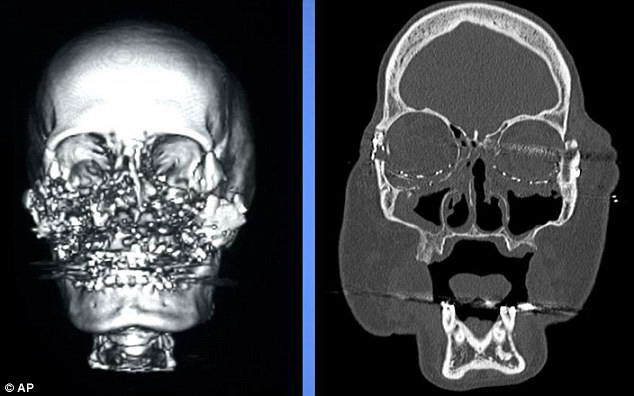

It looked like a skull Miss Culp before surgery, and began to look after.